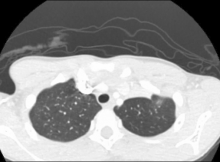

A 10-year-old boy presented with a carcinoid tumor obstructing the left upper lobe bronchus. He underwent VATS sleeve lobectomy. Initially, the authors attempted to perform a bronchotomy with reconstruction, however this distorted the bronchial reconstruction, resulting in poor re-expansion of the lower lobe. The resection was completed to a formal sleeve, and the primary reconstruction performed with good re-expansion of the lower lobe.